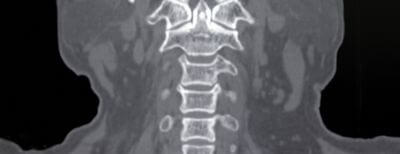

Комп'ютерна томографія (КТ) – це метод медичної візуалізації, який використовує рентгенівські промені для отримання високодеталізованих зображень поперечного перерізу тіла. КТ може допомогти діагностувати широкий спектр захворювань голови та шиї, включаючи пухлини, інфекції та інші патології.

КТ є цінним інструментом у діагностиці та лікуванні травм голови та шиї, включаючи переломи черепа, черепно-мозкові травми, а також травми хребта та шиї.

На закінчення, КТ-сканування є дуже універсальним і цінним інструментом у діагностиці та лікуванні широкого спектру захворювань, що вражають область голови та шиї. Хоча комп'ютерна томографія має певні обмеження та потенційні ризики, переваги КТ з точки зору точності, швидкості та неінвазивності роблять її важливим інструментом для лікарів та медичних працівників. Надаючи детальні, поперечні зображення внутрішніх органів і тканин, КТ-сканування допомагає революціонізувати спосіб діагностики та лікування захворювань голови та шиї.